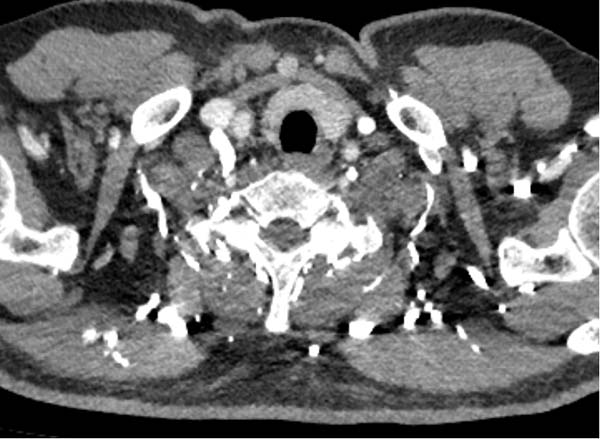

4) 右侧上肢血管畸形或闭塞。

右锁骨下堵塞导致肺动脉充盈欠佳